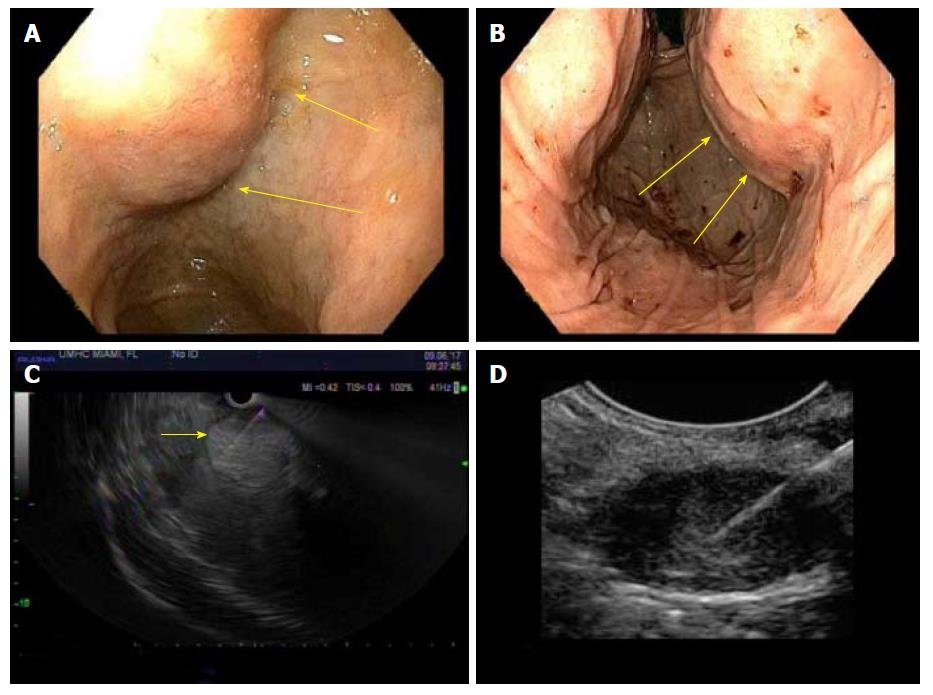

Endoscopy & Abdominal Scans

Visual diagnosis of ulcers, inflammation, and structural issues in your GI tract.